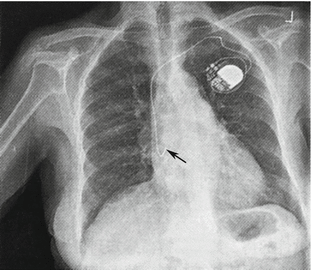

Right atrium pacemaker is also known as atrial-inhibited pacing (AAI). This is a relatively rare type. The electrode is placed in the right atrium, usually the right auricle (Figs. 4.22 and 4.23). The pacemaker can sense patients’ own electrical activities in the right atrium. If the rate of sinus pulse is higher than the preset level, the pacemaker is inhibited. Otherwise, the pacemaker will work continuously.

Fig. 4.22

X-ray shows the right atrium pacemaker that has been implanted under the left shoulder. The electrode passes through the subclavian vein while its head end in the right auricle